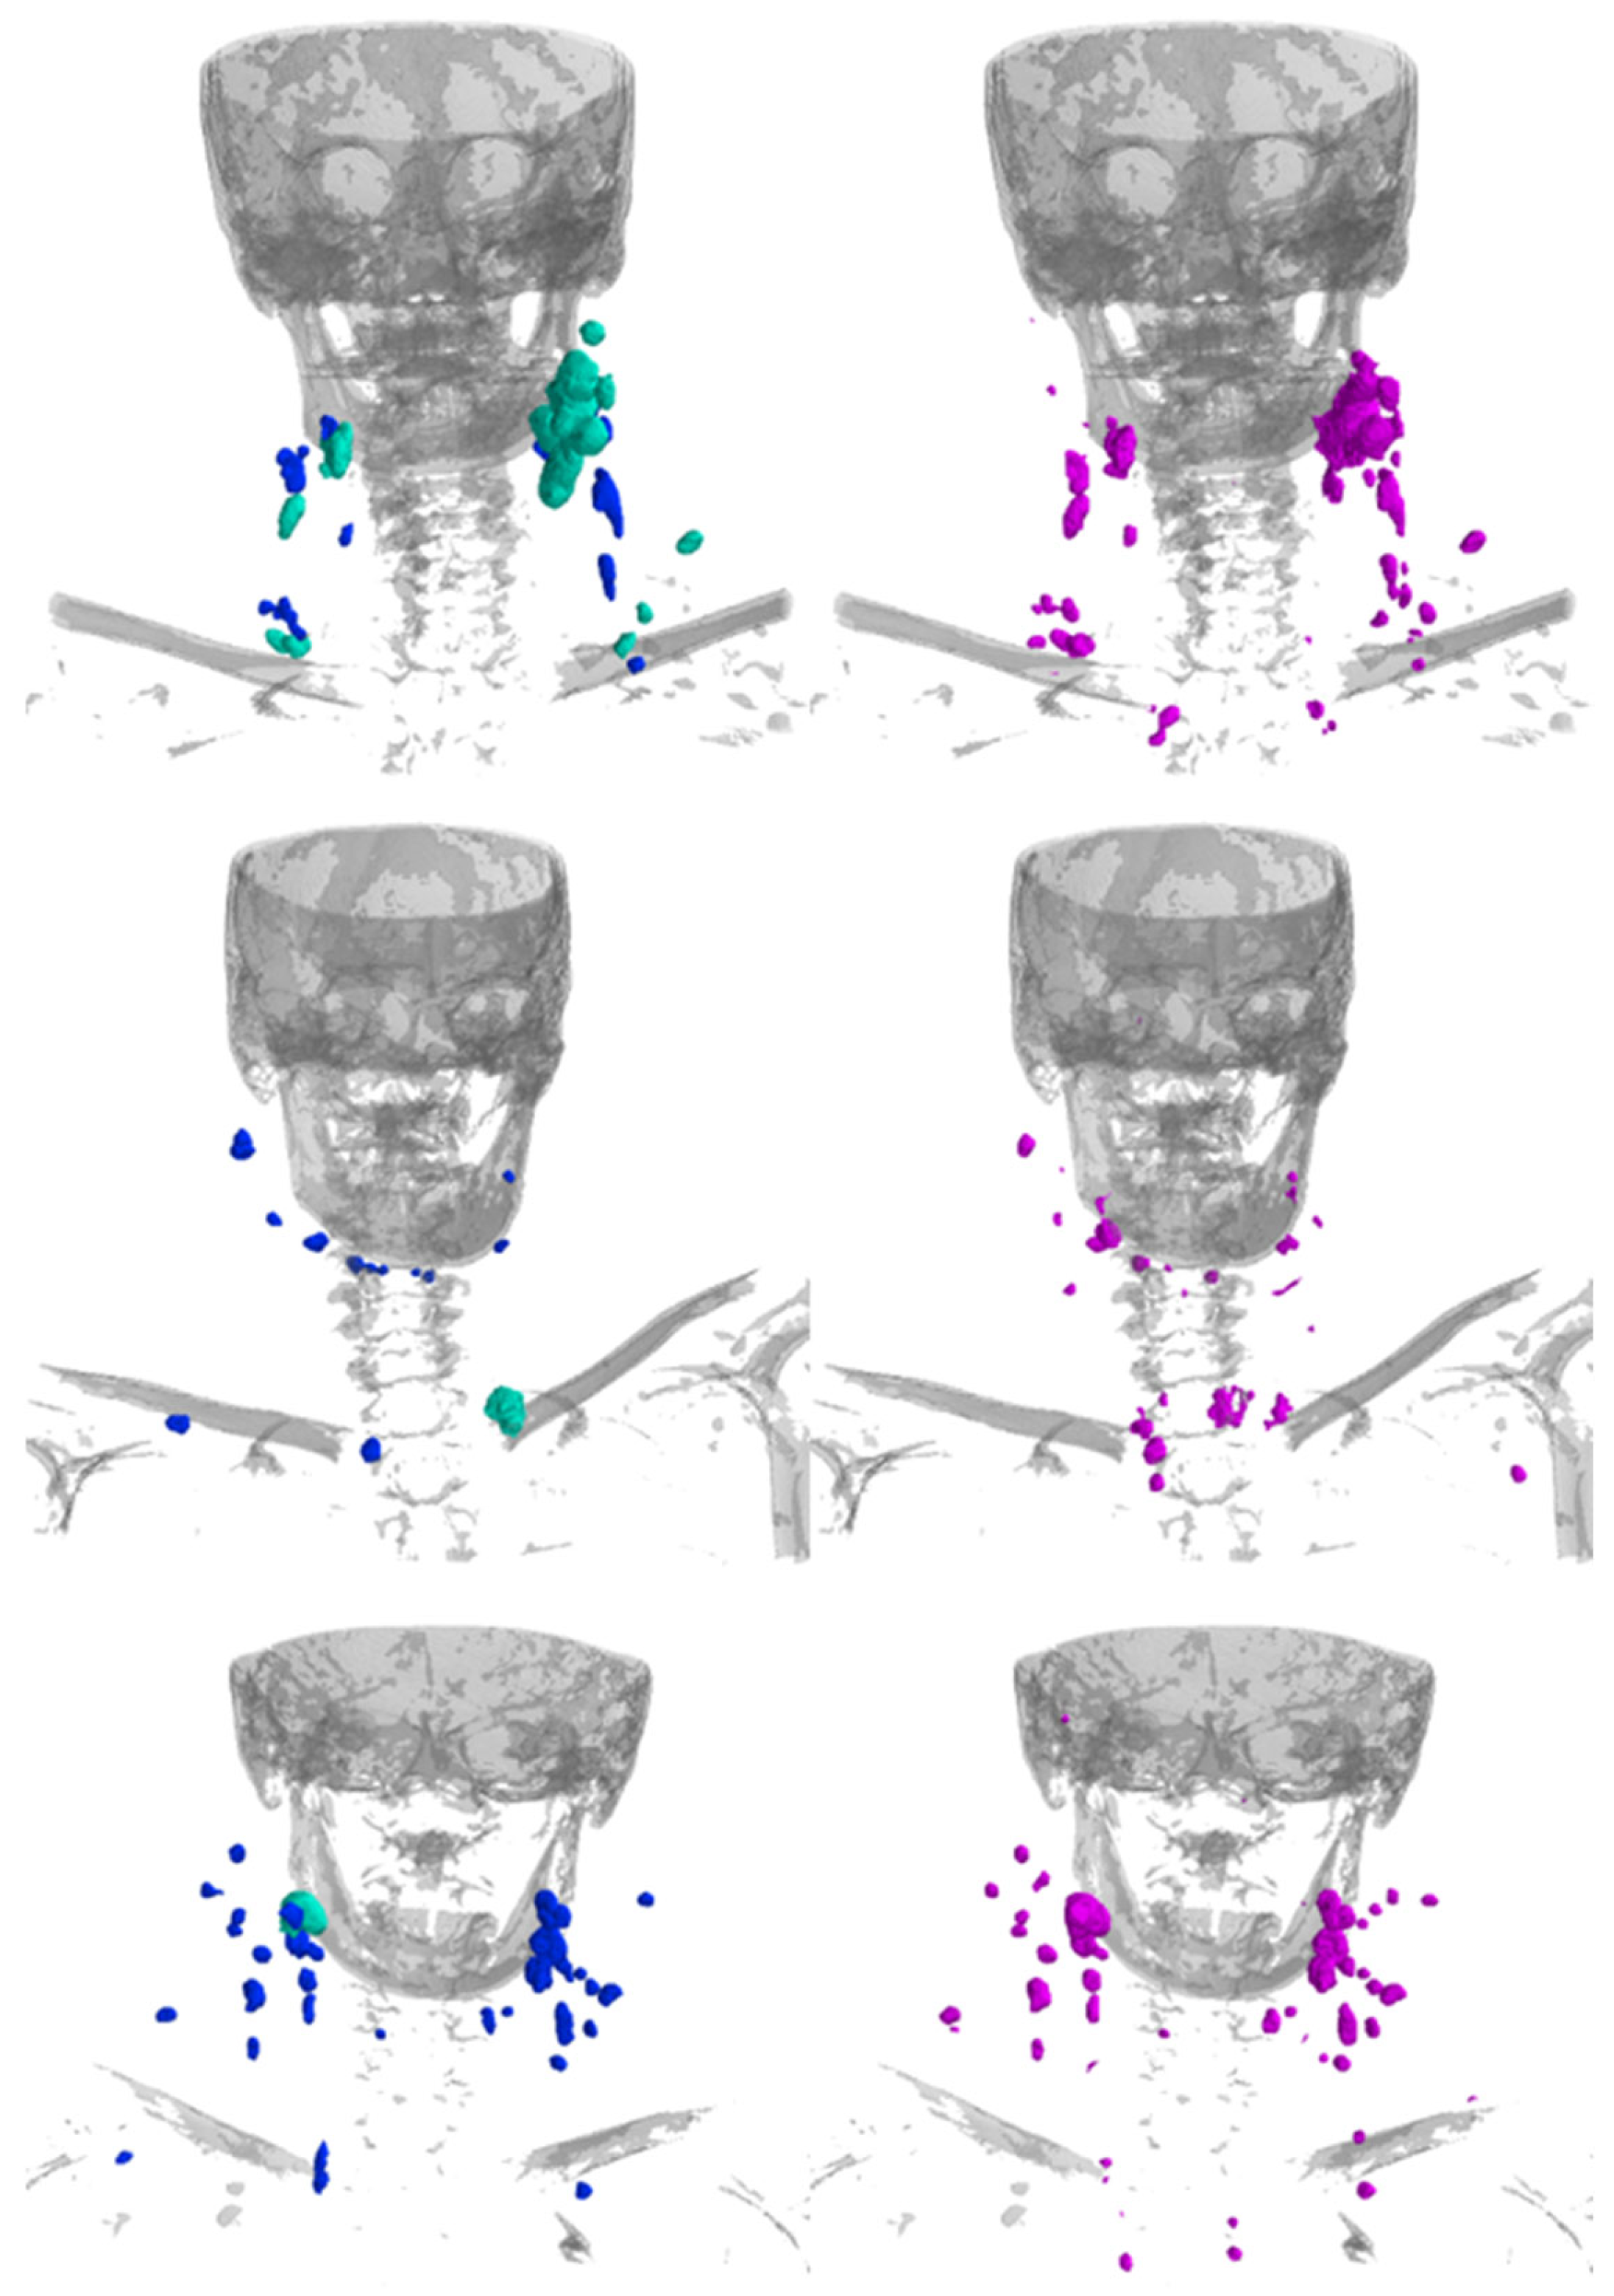

Example cases for visual comparison of the predicted and manual segmentations can be seen in Figure 4. The visual inspection shows good performance independent of the location and size of the LNs.

Figure 4.

Example renderings of the LNs showing the manual segmentations (left; blue = non-metastatic, cyan-green = labeled as clinically metastatic) and the segmentations predicted by the model (right; magenta). Bones are rendered in gray for anatomical orientation.